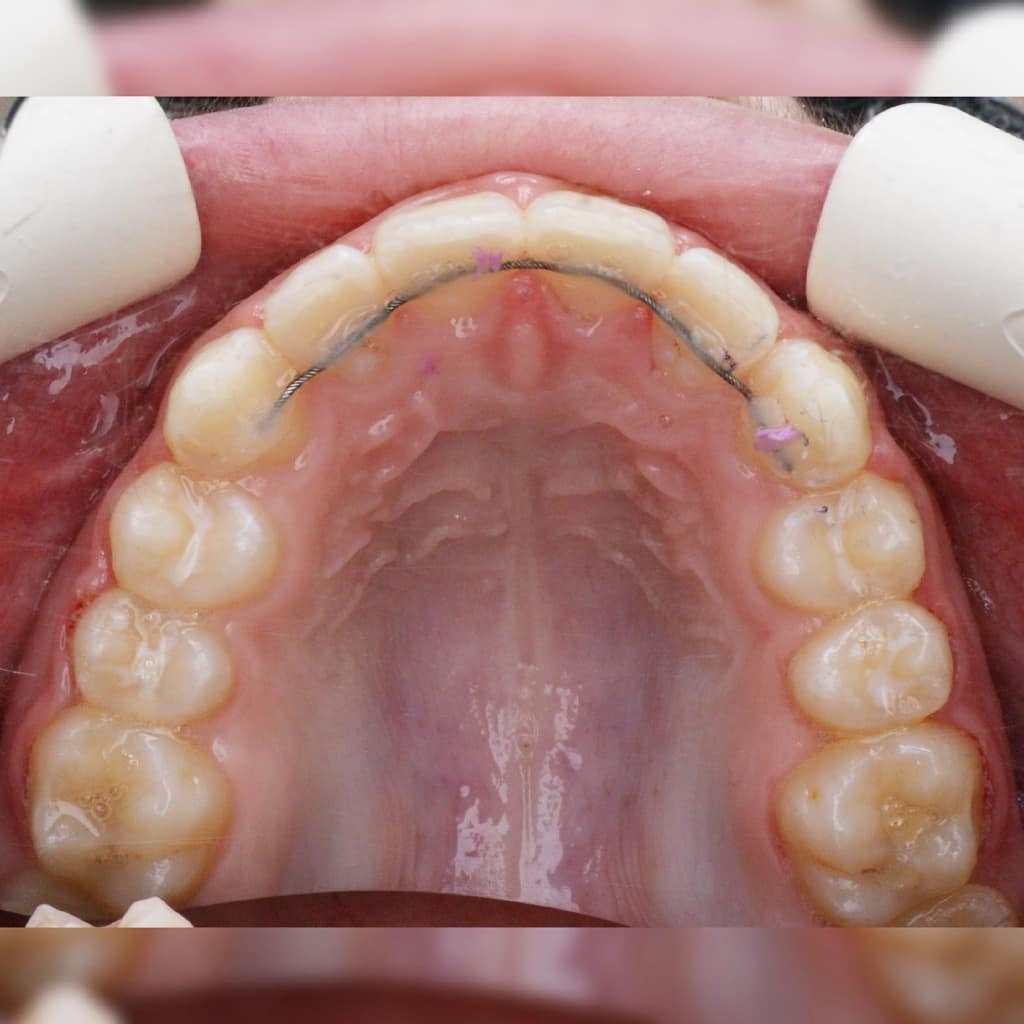

КАК УСТАНАВЛИВАЕТСЯ АППАРАТ МАРКО РОСА (Marco Rosa)

1️⃣ Установка сепарационных колец (голубые резиночки) в промежутки между опорными зубами для их небольшого раздвижения друг от друга и создания места для колец аппарата. Устанавливаются на 10-20 минут (могут устанавливаться на несколько дней).

2️⃣ Очистка опорных зубов от налёта с помощью специальной пасты и вращающейся щеточки бормашины.

3️⃣ На кольца наносится специальный стоматологический клей. Аппарат фиксируется во рту. Клей отверждается световой лампой. Добавляется клей на лапки молочных клыков.

КОНСТРУКЦИЯ АППАРАТА МАРКО РОСА

1️⃣ ВИНТ ХАЙРЕКС. Создаёт расширяющее усилие.

2️⃣ МЕТАЛЛИЧЕСКИЕ ЛАПКИ. Это дополнительные элементы фиксации, которые упираются в молочные клыки, создают точки приложения силы к зубному ряду.

3️⃣ КОЛЬЦА НА МОЛОЧНЫЕ МОЛЯРЫ. Обеспечивают фиксацию аппарата на опорных зубах с помощью специального стоматологического клея.

4️⃣ ПЛАСТМАССОВЫЙ БАЗИС (пластинка). Объединяет все элементы в единую систему и передаёт расширяющее усилие винта на нёбо.

5️⃣ ДОПОЛНИТЕЛЬНЫЕ ЭЛЕМЕНТЫ (крючки для лицевой маски)

*️⃣ Спанч Боб и Патрик😀

Аппарат Марко Роса (Marco Rosa) - маленький невидимый помощник в больших ортодонтических делах💗